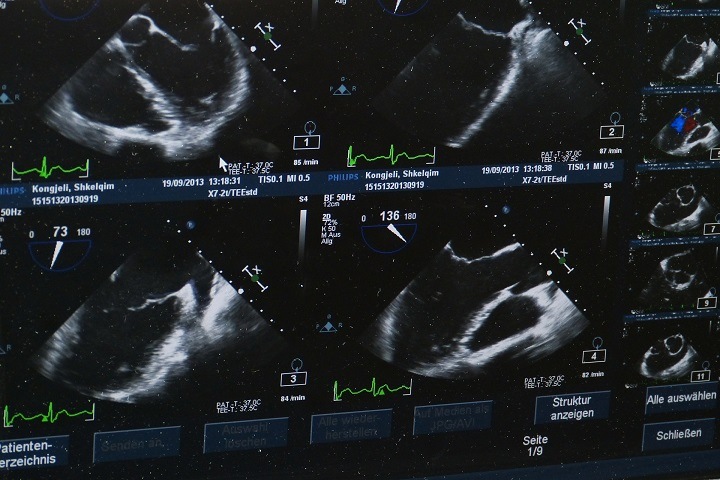

Оборудование высокого уровня разрешения обеспечивает четкое изображение, возможность рассмотреть снимок в мельчайших деталях. Устройства оснащаются множеством дополнительных функций, что делает их многофункциональными. Современные УЗИ с экспертным классом относятся к категории дорогостоящего оборудования.

разрешающая способность; удобство в использовании; наличие высокоплотных датчиков; набор заложенных программ; способность визуализировать тонкие детали; на готовых снимках видна структура органов, сосудов и тканей.

Экспертное оборудование полезно на стадии диагностирования заболеваний и патологий. При ультразвуковом исследовании получается четкий снимок, с помощью которого можно диагностировать заболевания внутренних органов организма на ранней стадии. Врач может поставить точный диагноз при размытой клинической картине. Своевременно и правильно назначенное лечение повышает шансы на полное выздоровление, снижает вероятность побочных эффектов и ухудшения состояния больного.